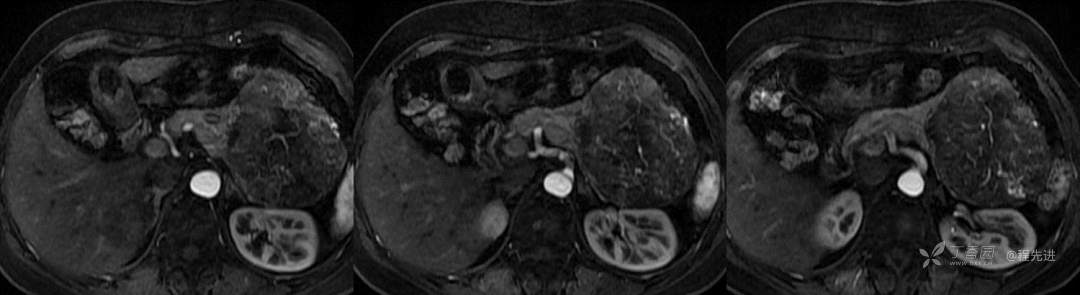

T2压脂

DWI

ADC

ADC 值:2.8×10-3mm2/s